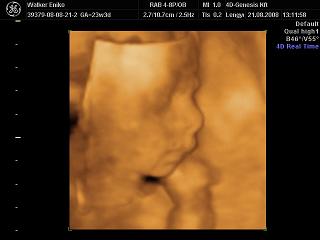

Nagyon helyesek a 4D-s fotók!!!